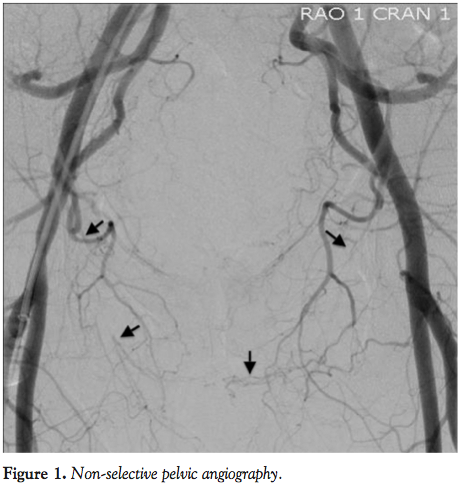

A 49-year-old man with a history of coronary artery disease, s/p multiple prior coronary interventions, peripheral arterial disease, insulin-dependent diabetes, dyslipidemia, hypertension, and chronic kidney disease presented with severe erectile dysfunction refractory to PDE5i therapy. A 5 Fr, 12 cm sheath was initially placed in the left common femoral artery and non-selective angiography was performed with a pigtail catheter in the descending aorta in the flat anterior-posterior (AP) view. This permitted evaluation of the common and

internal iliac arteries as well as distal runoff of both internal pudendal arteries to the penis. Angiography revealed bilateral proximal occlusions of the pudendal arteries with distal reconstitution (Figure 1). The distal segment of the right reconstituted pudendal artery was better visualized and seemed to be less diseased compared to the left. Therefore, the right pudendal artery was felt to be a better target vessel for revascularization. A short sheath was exchanged for a 5 Fr, 45 cm, hydrophilic-

A 12 cm, 5 Fr sheath was placed in the right common femoral artery. Non-selective angiography was performed with a 5 Fr pigtail catheter in the descending abdominal aorta demonstrating bilateral occlusion of pudendal arteries. Angiography and successful endovascular revascularization of the left leg were then performed for identified severe PAD. This was performed via a 7 Fr, 45 cm sheath that was advanced with the tip in the left common femoral artery. The sheath was then pulled back to the ostium of the left internal iliac artery and a 0.035˝ wire was advanced into the left internal iliac artery. Due to the fact that the proximal segment of the left internal iliac artery was large and healthy, we advanced the sheath into the proximal segment over the 5 Fr IM catheter, which was used to redirect the wire and facilitate the sheath advancement. Selective angiography of the left internal iliac system was then performed at flat AP position, 30° RAO angulation, and 30° LAO angulation. It demonstrated diffuse, severe disease in the left internal pudendal artery with long segments of total occlusions (Figure 5). The left internal pudendal artery arose directly from the left internal iliac artery. A 5 Fr, angled, hydrophilic-coated catheter was advanced through the sheath and directed toward the left internal pudendal artery to facilitate wire passage through the lesions. However, a 0.014-300 cm coronary wire crossed only the proximal segment of the stenotic lesion and the rest of the lesion was crossed only after we used coronary 2.0 x 20 mm over-the-wire balloon for support. Multiple inflations up to 16 atm were then performed with the same 2.0 x 20 mm over-the-wire balloon. Since this patient had a very long total occlusion, suboptimal angioplasty result, and a history of diabetes, we decided to use drug-eluting stents to achieve an optimal angiographic result as well as to minimize the risk of restenosis. We used two 2.5 x 30 mm drug-eluting coronary stents that were deployed in overlapping fashion at 12 atm. This led to a good angiographic result (Figure 6). This patient was discharged the same day and had no complications. At clinical follow-up, the patient reported significant improvement in erectile function with good response to PDE5i therapy.

Arterial access was achieved with placement of a 12 cm, 5 Fr sheath in the right common femoral artery. Non-selective digital subtraction angiography was performed with a 5 Fr pigtail catheter in the descending aorta, demonstrating patent internal iliac arteries and obstructive disease of the left pudendal artery. A 5 Fr internal mammary guide catheter was advanced over a 0.035-260 cm, stiff-shaft, angled hydrophilic wire and positioned at the ostium of the left internal iliac artery. Digital subtraction angiography at the flat AP position, 30° RAO, and 30° LAO angulation demonstrated severe disease in the left internal pudendal artery (Figure 7 RAO and Figure 8 AP).